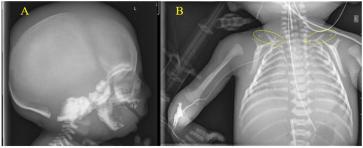

Chorio-amniale Separation bei einem Feten mit restriktiver Dermatopathie

Das Amnion und das Chorion fusionieren mit dem Beginn des zweiten Trimenons zur eigentlichen Fruchtblase. Die Chorionhöhle obliteriert somit kontinuierlich und sollte mit 14 bis 16 Wochen verschwunden sein. Eine chorio-amniale Separation (CAS) kann sekundär oder primär auftreten. Sekundär z. B. nach invasiven diagnostischen (z. B. Amniozentese) oder therapeutisch-fetoskopischen Eingriffen. Man kann das auch gelegentlich bei Mehrlingsschwangerschaften, bei massivem Polyhydramnion und auch nach hohem Blasensprung beobachten, dann meist lokalisiert, kann sich aber auch ausdehnen zu einer vollständigen Ablösung des Amnions (1). Diese sekundären Formen einer CAS kann man sich somit gut erklären. Die primären sind indes etwas komplexer. Meines Erachtens sind sie als Ausdruck einer grundlegenden Störung der extrazellulären Matrix (ECM) zu verstehen. Tatsächlich wird eine primäre CAS gelegentlich bei Trisomie 21, 18 und 13 beschrieben. Diese Trisomien gehen mit einer Reifungsstörung der ECM einher, welche auch die pathologische Nackentransparenz erklärt (2, 3). Aber auch bei Fällen mit restriktiven Dermatopathien (RD) wurden CAS beschrieben (4). Diese Beobachtungen unterstreichen die Tatsache, dass sowohl das Amnion wie die Haut ektodermalen Ursprungs sind. Ja, unser Fall entpuppte sich erst nach Geburt als ein Kind mit einer leider letalen RD. Der primäre Pathomechanismus dieser Störungen ist weiterhin wenig geklärt. Aber ähnlich den Veränderungen der ECM bei den Trisomien ist bei den Fällen mit RD die Haut charakterisiert durch eine abnorme Akkumulation von Kollagenen und fehlenden elastischen Fasern. Es sind seltene, autosomal rezessive (seltener dominante) Mutationen klinisch charakterisiert durch eine dünne, durchscheinende und rigide Haut (Bild 1), mit Gesichtsdysmorphien (kleine Nase und kleiner Mund, Micrognathie, tiefsitzende Ohren, weite Fontanellen) und multiple Gelenkskontrakturen neben Wachstumsrestriktion und auch sonstige Skelettauffälligkeiten (Bild 2, 3) (5). In unserem Fall wurde eine autosomal rezessive Mutation im ZMPSTE24-Gen gefunden. Diese Mutation führt in homozygoter Version (beide Eltern Träger!) zu diesen klinischen und morphologischen Besonderheiten (6).